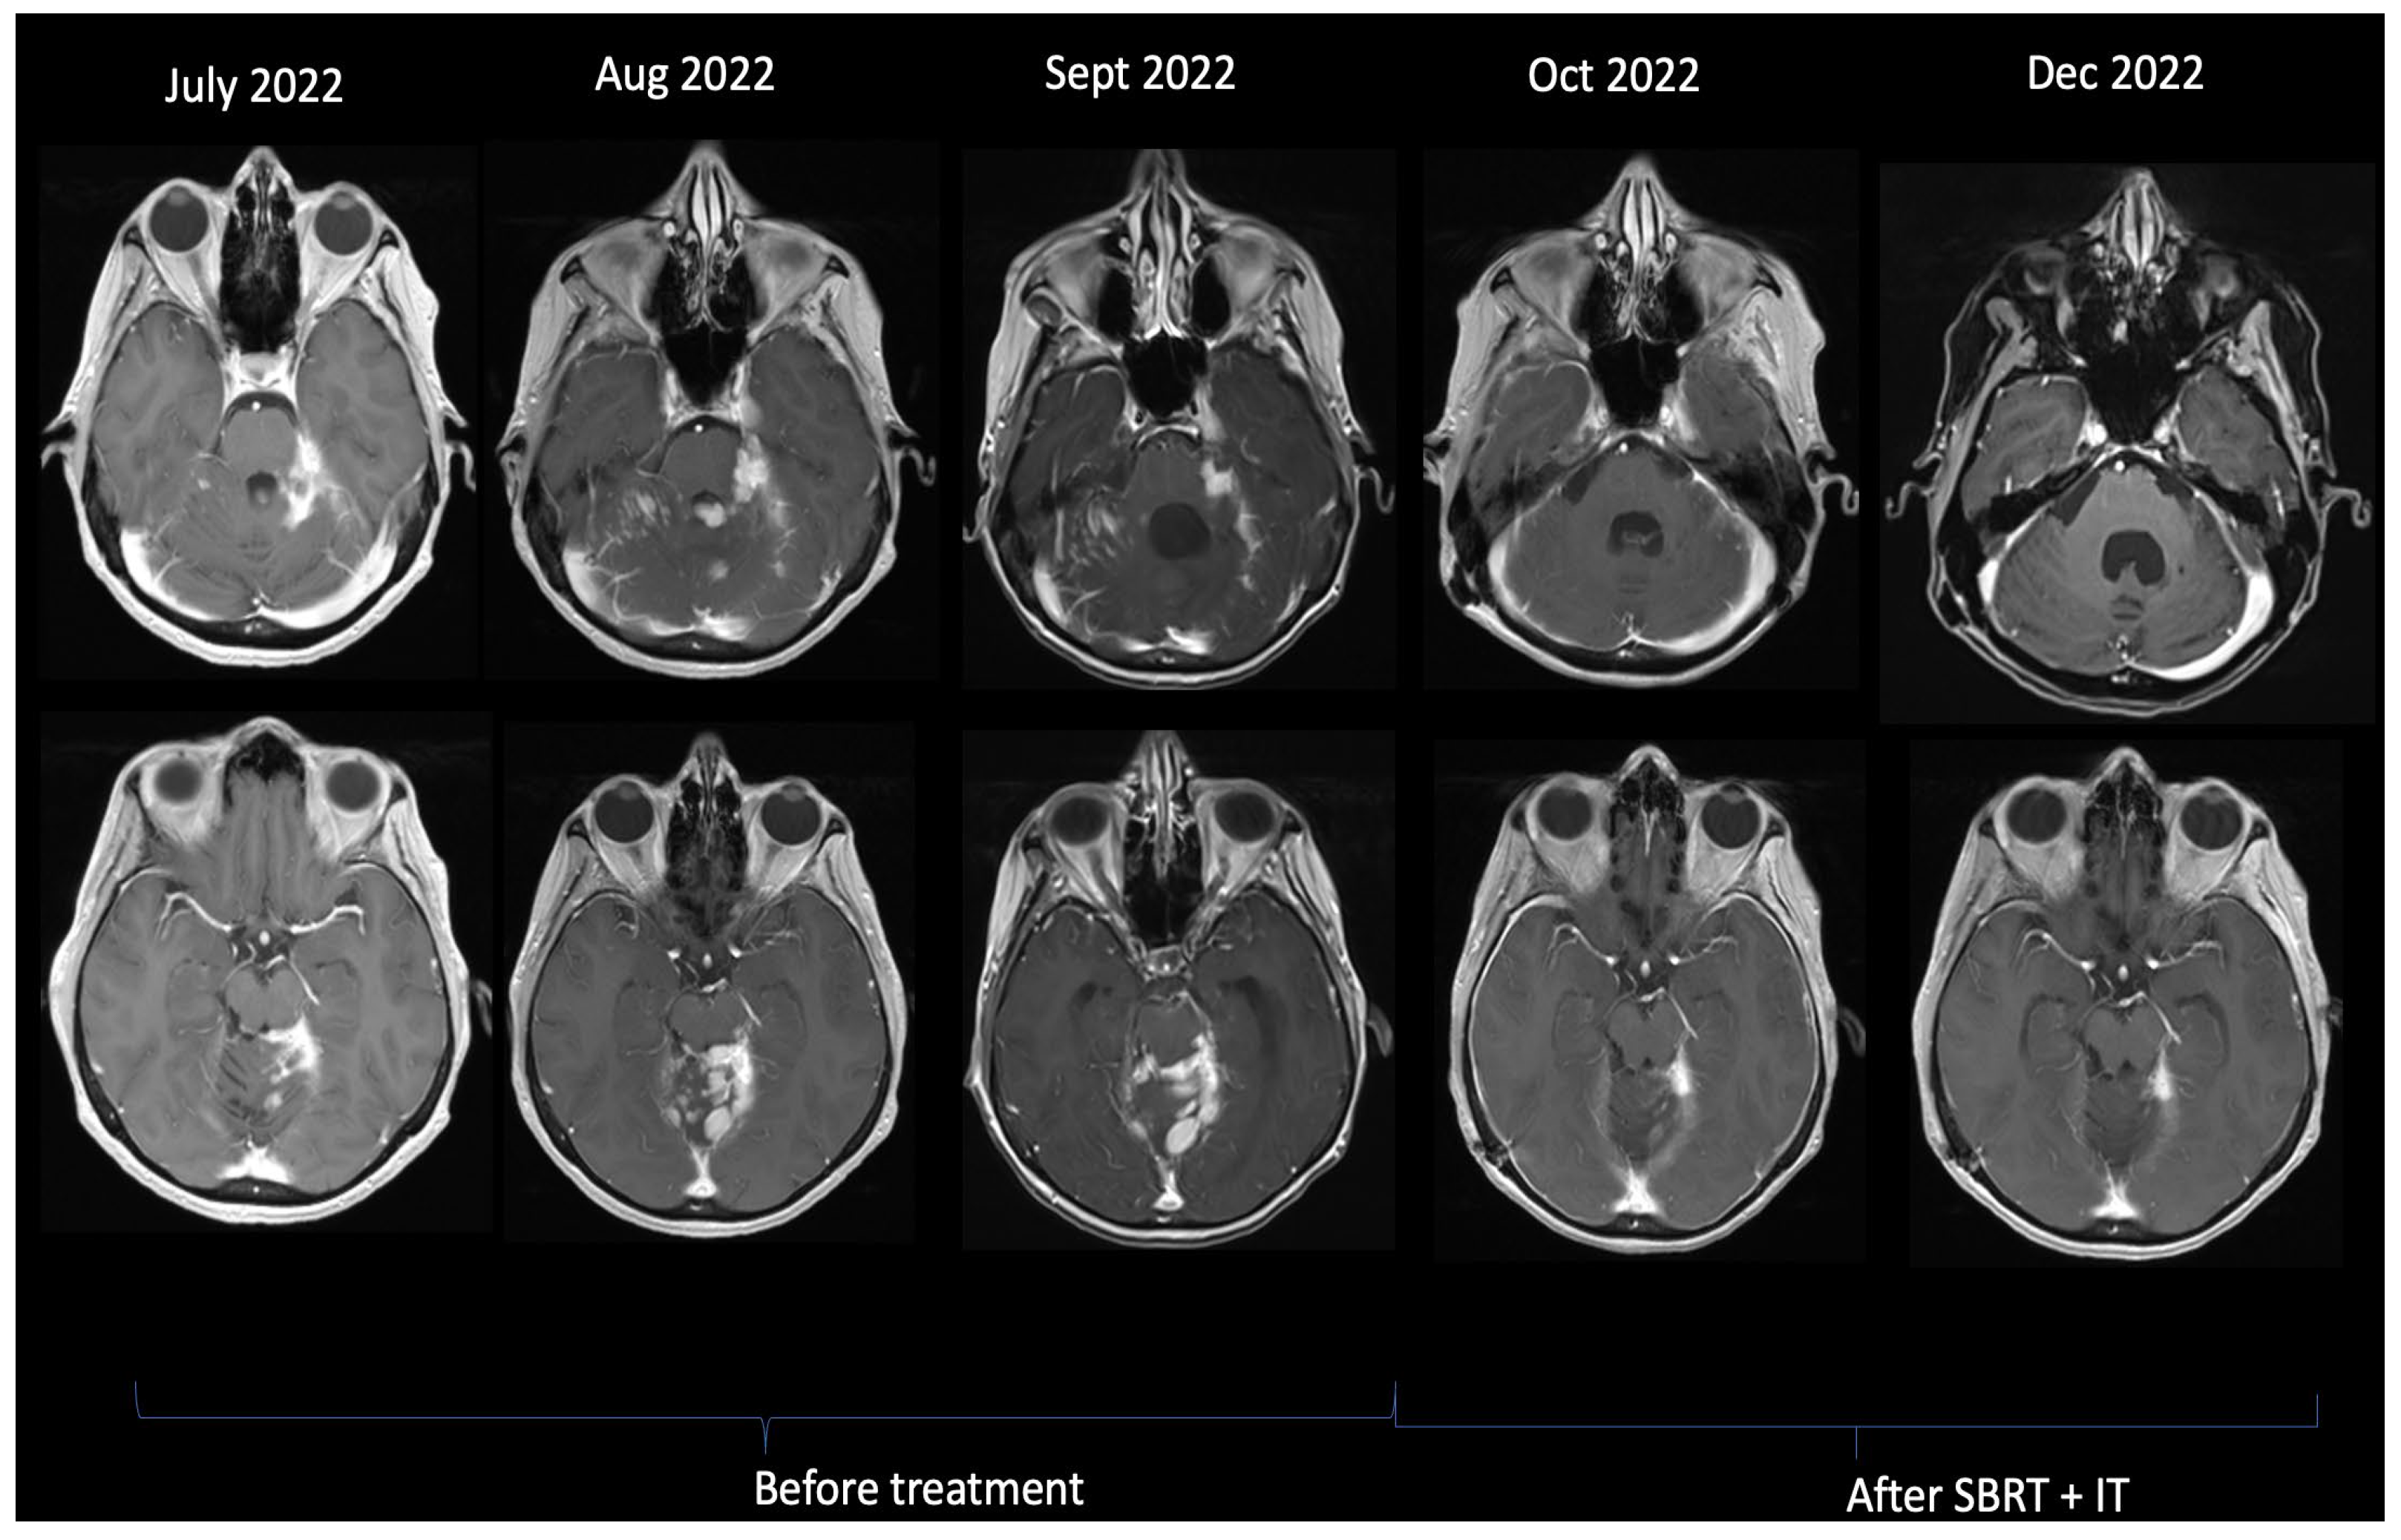

| 1. | 54 | 100 | 13 | Yes | Yes | Yes | 41 | C | 12 | No | Tucatinib-Capecitabine-Trastuzumab | 18 | 19 |

| 2. | 38 | 100 | No BM | No | No | Yes | 0 | B | 35 | No | Tucatinib-Capecitabine-Trastuzumab | 24 | 24 |